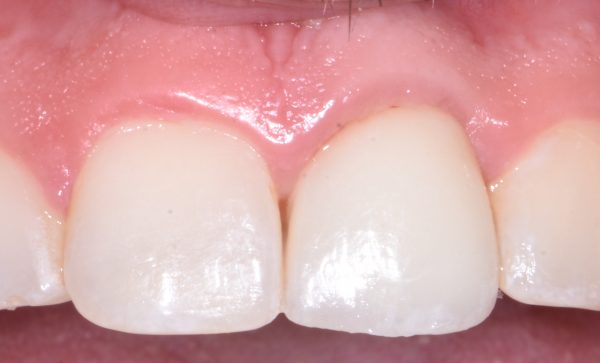

Implant Crown (one tooth)

- Implant crown: Ideal for replacing a single missing tooth.